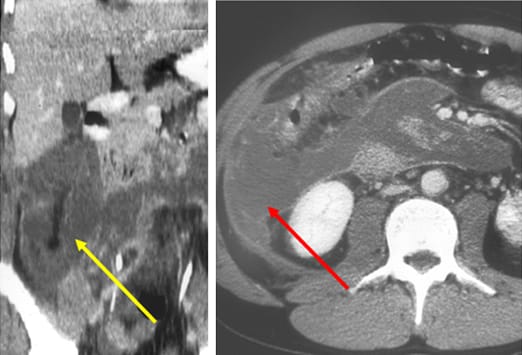

Intravenöses Kontrastmittel (siehe Abbildung) ist ein wichtiges diagnostisches Hilfsmittel. Dieser Patient präsentierte sich mit einer Hypotonie und einer gram-negativen Sepsis, allerdings ohne abdominelle Schmerzen in der klinischen Untersuchung. Das Bild auf der linken Seite, welches mit oralem, aber ohne intravenöses Kontrastmittel durchgeführt wurde, ergab keinen schlüssigen Befund. Das Bild auf der rechen Seite zeigt die erneute Untersuchung nach Gabe von intravenösem Kontrastmittel. Dieses stellt eine verdickte, vermehrt kontrastierte Appendixwand und entzündliche Veränderungen des umgebenden Fettgewebes dar.